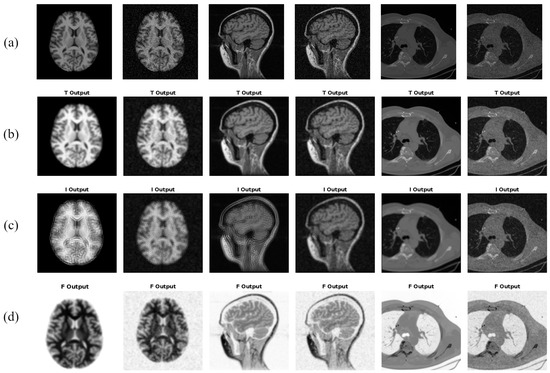

- A new idea of using neutrosophic information for extracting underlying textures from medical images. Neutrosophic images offer flexibility in representing texture information by allowing each pixel to have varying degrees of truth, indeterminacy, and falsity. This flexibility accommodates the diverse and complex nature of texture patterns in medical images, providing a more adaptable framework for feature extraction.

- A new approach, , is presented that extracts texture features from all three neutrosophic images, i.e., truth (T), indeterminacy (I), and falsity (F). The texture features from each of the T, I, and F images are appended together to form the final feature vector for .

- Firstly, the medical image is transformed to the neutrosophic domain, such that for every input medical image, we obtain three neutrosophic images, i.e., truth (T), indeterminacy (I), and falsity (F).

2.1. Construction of Neutrosophic Images